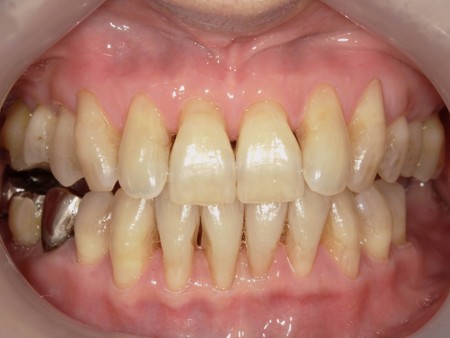

治療前

| カウンセリング・診断結果 | お話を伺うと長年コーヒー、紅茶などを好んで飲食されていたとの事でした。 全顎的に見られた歯磨きしても落ちない汚れは、飲食物由来によるステインと診断しました。 歯ブラシでは落とすのが困難で専用の機械による除去が必要になります。 |

・ステイン除去 ステインは広範囲に付着していると、保険の範囲内で綺麗に落とすには限界があります。 また、ステイン除去は自費のメンテナンスになります。着色除去専用の機械を使い、特殊なパウダーを使用し落としていきます。歯の表面を傷つけずに優しく落とすことが可能です。継続していく事で再付着しにくくなります。 ※ステインを除去することで歯本来の色味になりますが、それ以上白くなったりの色変化はありません。 ・ホワイトニング 何回か着色除去のメンテナンスを継続していましたが、「歯自体の色を明るくしていきたい」とのことでしたのでホワイトニングをご提案しました。 デュアルホワイトニング、オフィスホワイトニング、ホームホワイトニングの3種類からオフィスホワイトニングを選択していただきました。 患者さんは虫歯、歯周病等はありませんでしたのでご自身のタイミグでスタートしていきました。 ※当院のオフィスホワイトニングでは2回来院で施術を行って行きます。 |